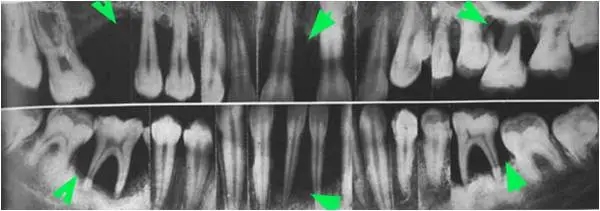

可能很多人都听说过,牙龈出血是牙周炎的主要症状之一。那么,牙龈好出血是不是意味着一定患上牙周炎了呢?如果不是,还有可能是什么问题呢? 不简单的牙周病 虽然一提到牙周病,我们往往最先想到的就是牙周炎,但从牙周病的专业分类角度讲,狭义的牙周炎(实为慢性牙周炎)只是近十种牙周病中的一种而已。根据目前的分类方法,牙周病首先可以分为牙龈病和牙周炎两大类,而牙龈病和牙周炎再分别分为若干类型。慢性牙周炎的确是牙周炎类别中最常见的类型。 牙周炎的临床症状主要有四点:牙龈炎症和出血、牙周袋形成、牙槽骨吸收以及牙齿松动和移位。因此,牙龈出血确实是能够反映牙周炎存在与否的客观指标之一。然而反过来,牙龈出血却并不能和发生牙周炎划等号。这是因为,在牙周病分类中,牙龈病中最常见的一类是牙龈炎,它也是会引起牙龈出血的。因此,当有牙龈出血症状存在的时候,病人既可能是患了牙周炎,也可能是患了牙龈炎。 同为牙周病,又同样有牙龈出血症状,如何判断是牙龈炎还是牙周炎呢? 牙龈炎和牙周炎的差异源于两者的病变范围不同,前者炎症仅累及牙龈组织,而后者则是牙龈炎的基础上,更深层的组织——牙周膜、牙槽骨和牙骨质也被累及,因而两者的表现还是有很明显的差别的。 重要的是要“看穿它” 单凭牙龈出血这一个症状,非专业人员是没办法区分牙龈炎和牙周炎的,只有专业医生用专业办法才能对它们予以区分。 牙周炎,一方面会出现更加严重的牙龈炎症——牙龈在出血的同时,还会与牙面分离,就像被掀开一样,并形成所谓的牙周袋;另一方面则表现为更深层牙周组织的炎症,牙周膜和牙槽骨因此遭到破坏。当破坏范围达到一定程度时,牙齿可能松动、甚至移位。对我们来说,最关键的问题是要尽早发现组织破坏的苗头。 那么,什么方法可以帮助我们发现这些苗头呢?牙医有两大法宝:牙周探针和全景片。 在口腔常规检查中,有一种器械叫探针。而牙周探针与普通探针不同,有两个特点:一是针头末端圆钝,二是针头有刻度。这些特点与它的用途关系密切——它主要是用于检查牙周袋的,即对牙周袋的位置和深浅做探测。末端圆钝可以避免它对牙龈造成刺痛和刺伤,有刻度可以使它能够显示出牙周袋的深浅。 正常的牙龈也有小部分是与牙面分离的,这部分牙龈即可与牙面之间形成一条浅沟——牙龈沟。但牙龈沟的深度通常在3 mm以内。牙周袋则不同,它的深度可能达到5~10 mm,它形成的基础是一方面源于牙龈与牙面分离的部分增加,另一方面则源于牙龈萎缩的速度慢于牙龈与牙面分离的速度。很显然,牙周袋的深浅可以反映出牙周炎的严重程度。 在口腔常规检查中,放射线检查也是很常见的检查方法。而在牙周病检查诊断过程中,最常用的方法是拍全景片,其学名是全口曲面体层片。它的突出优势是可以将整口牙的牙槽骨情况尽收眼底。通过全景片,牙医可以看到牙槽骨是否有吸收,以及发生吸收的牙位、严重程度等,由此辅助诊断牙周炎是否存在和制定牙周治疗计划。牙槽骨吸收的情况也可以反映出牙周炎的严重程度。但这个指标不能凭肉眼判断,只有放射线检查才能帮助我们“看穿”牙槽骨的内部情况。 因此,要确认是牙龈炎还是牙周炎,不能单凭猜测,只有通过专业手段做检查后才能下结论。 有牙龈炎≠必有牙周炎 虽然说到这,大家已经知道怎么区分牙龈炎和牙周炎了,但仍有人会担心“我的牙龈炎会不会发展为牙周炎?”虽然两者都有牙龈的损害,但牙周炎却并非牙龈炎的“升级版”。换言之,一个人现在有牙龈炎并不意味他未来一定会有牙周炎,因为不是所有牙龈炎都会发展为牙周炎。有研究资料显示,绝大多数人(81%)的牙龈炎病情发展缓慢,仅小部分人(8%)病情迅速加重,而另一部分人(11%)的病情静止,不发展为牙周炎。但也有研究认为,牙龈炎往往会被视作牙周炎的前驱症状和危险因素,因此积极预防牙龈炎也有重要意义。 因此,我们采取积极、客观的态度面对牙龈炎和牙周炎,才是正确选择。既不要漠然处之,也不要风声鹤唳草木皆兵。 作者:上海市卫生和健康发展研究中心 富饶 延伸阅读